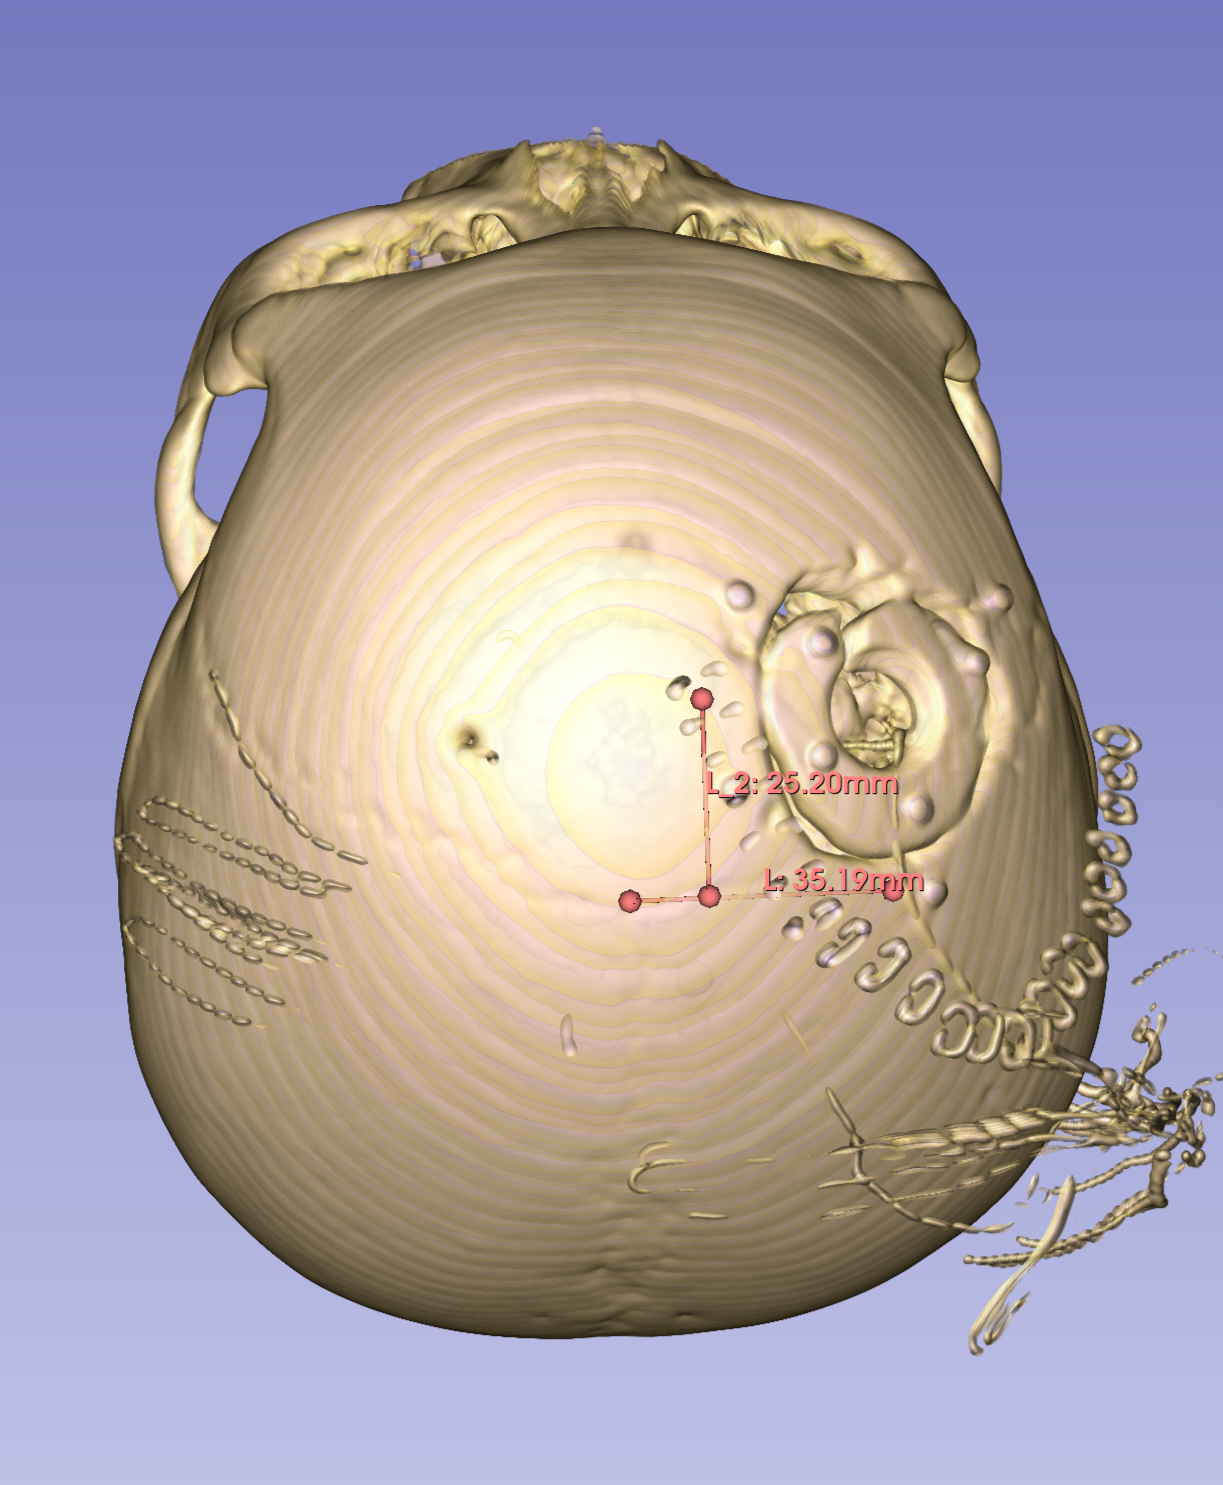

手术切口设计

骨窗中心位于中线旁开3.5cm冠状缝前2.5cm